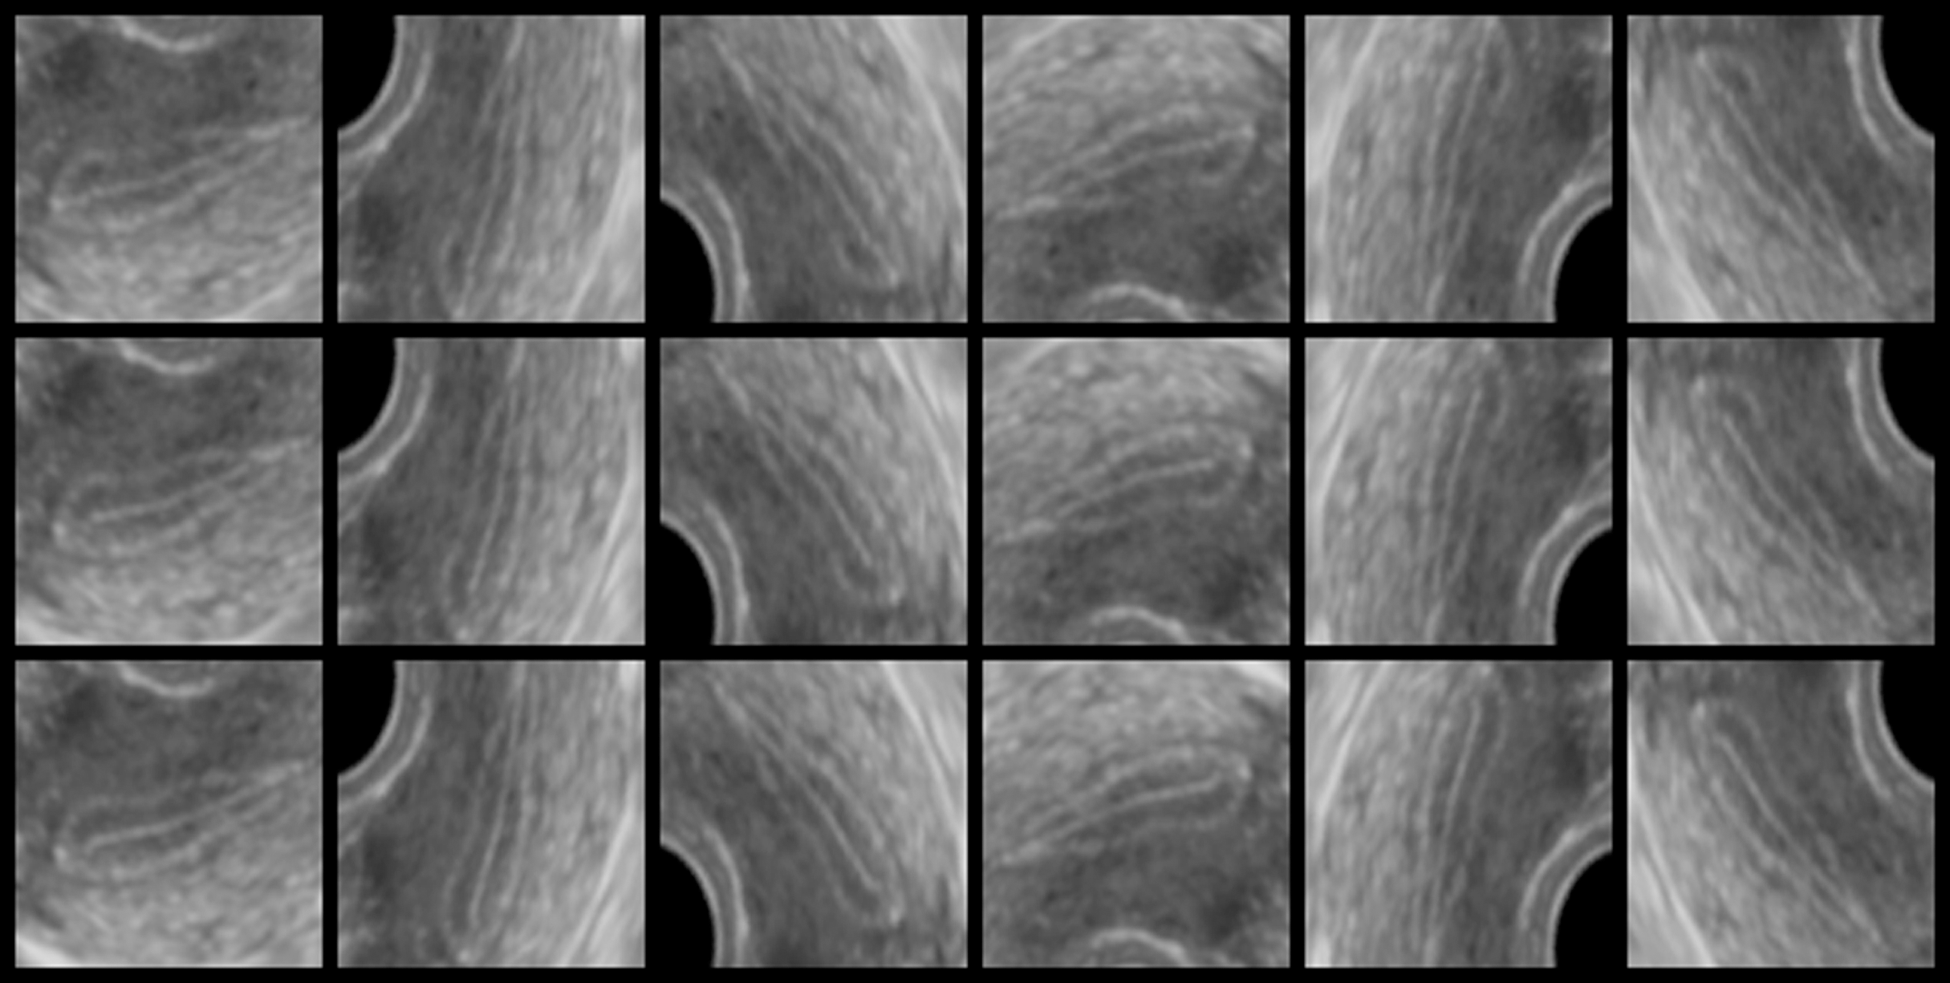

An averaging filter of 5 × 5 pixels is applied to the ultrasonic images as preprocessing. An average image is generated every second from the movie file by calculating an average for a time axis. 30 images are generated from 30 second movie by this process. An endometrial region is extracted from the average image by using a mask image. The mask image has been manually generated in advance. Fig. 2 shows original image, mask image, extracted image by the mask, and resized image. This mask works to extract endometrium region from ultrasonic images. Since an endometrial shape and direction have individual differences, the extracted region size is different from each other. Rotation processes every 60 degrees are applied to the extracted images. The obtained image is saved in 224 × 224 pixels. Fig. 2d shows the saved image of 224 × 224 pixel size. Fig. 3 shows example of the saved images. A vertical axis in Fig. 3 shows time of movie file, and horizontal axis shows rotated images. Tab. 4 shows the number of the saved images.

Figure 3: Example of the saved original images